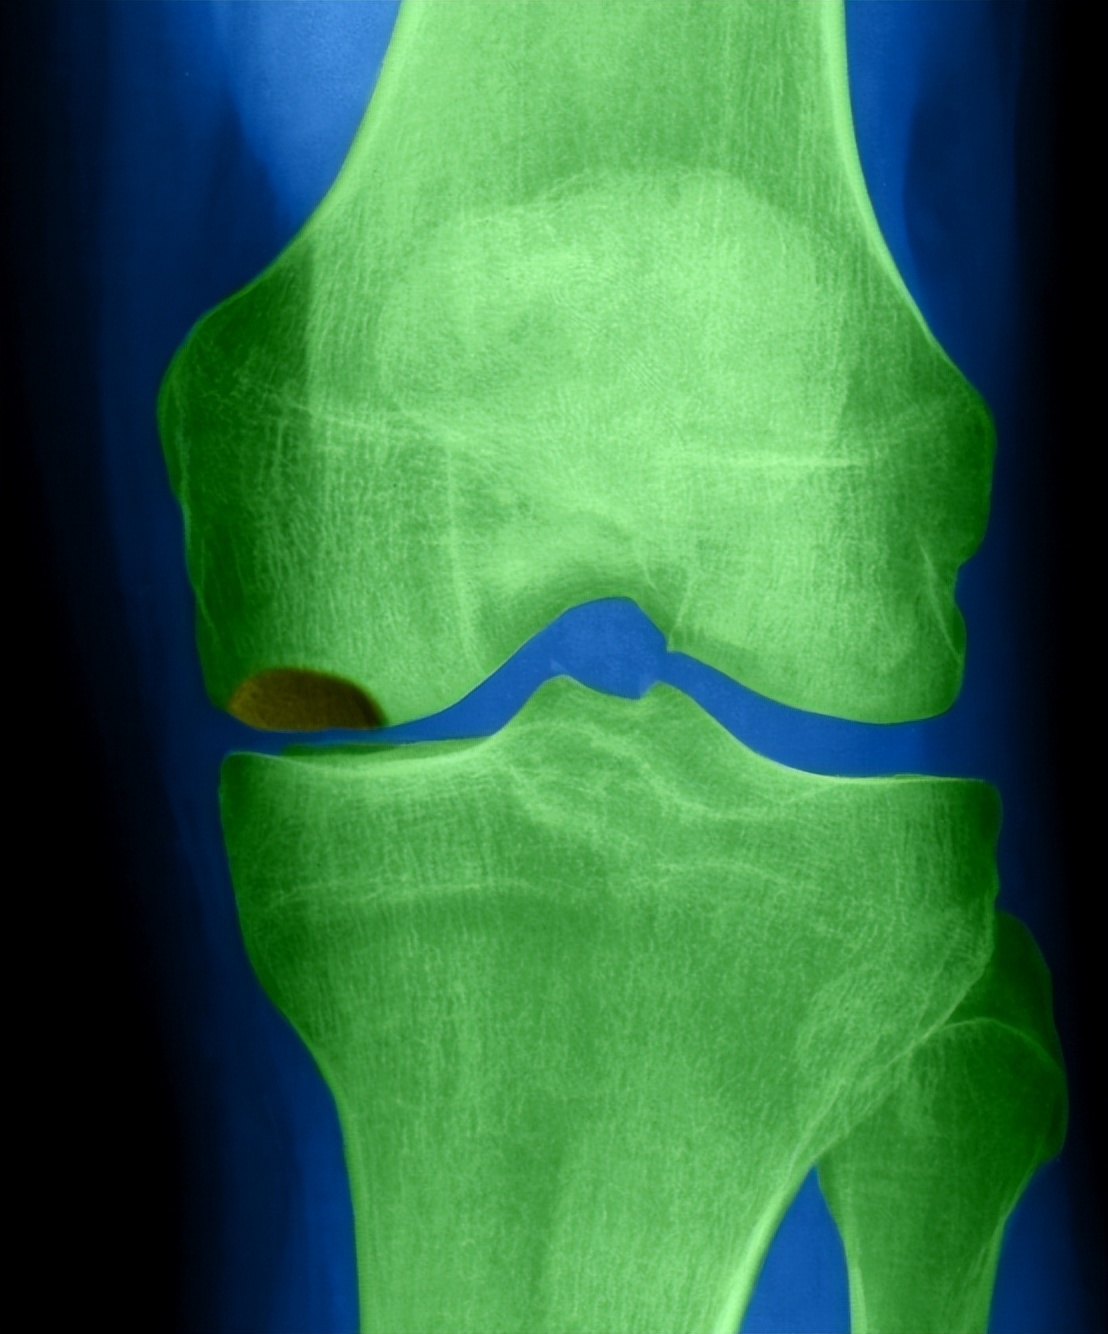

张大爷本想自己去医院检查,但是出门变得困难了。没办法给自己的儿子打个电话去医院检查。 经过诊断,张大爷的膝盖是骨关节炎,并且已经存在积水的问题,需要手术治疗。

在出现外伤或者长时间劳作的时候,部分关节出现肿大变形的情况,这些肿胀可能是关节出现关节积液造成的。 所以一旦关节肿大疼痛要及时去往医院进行拍片检查,确认病因进行治疗。